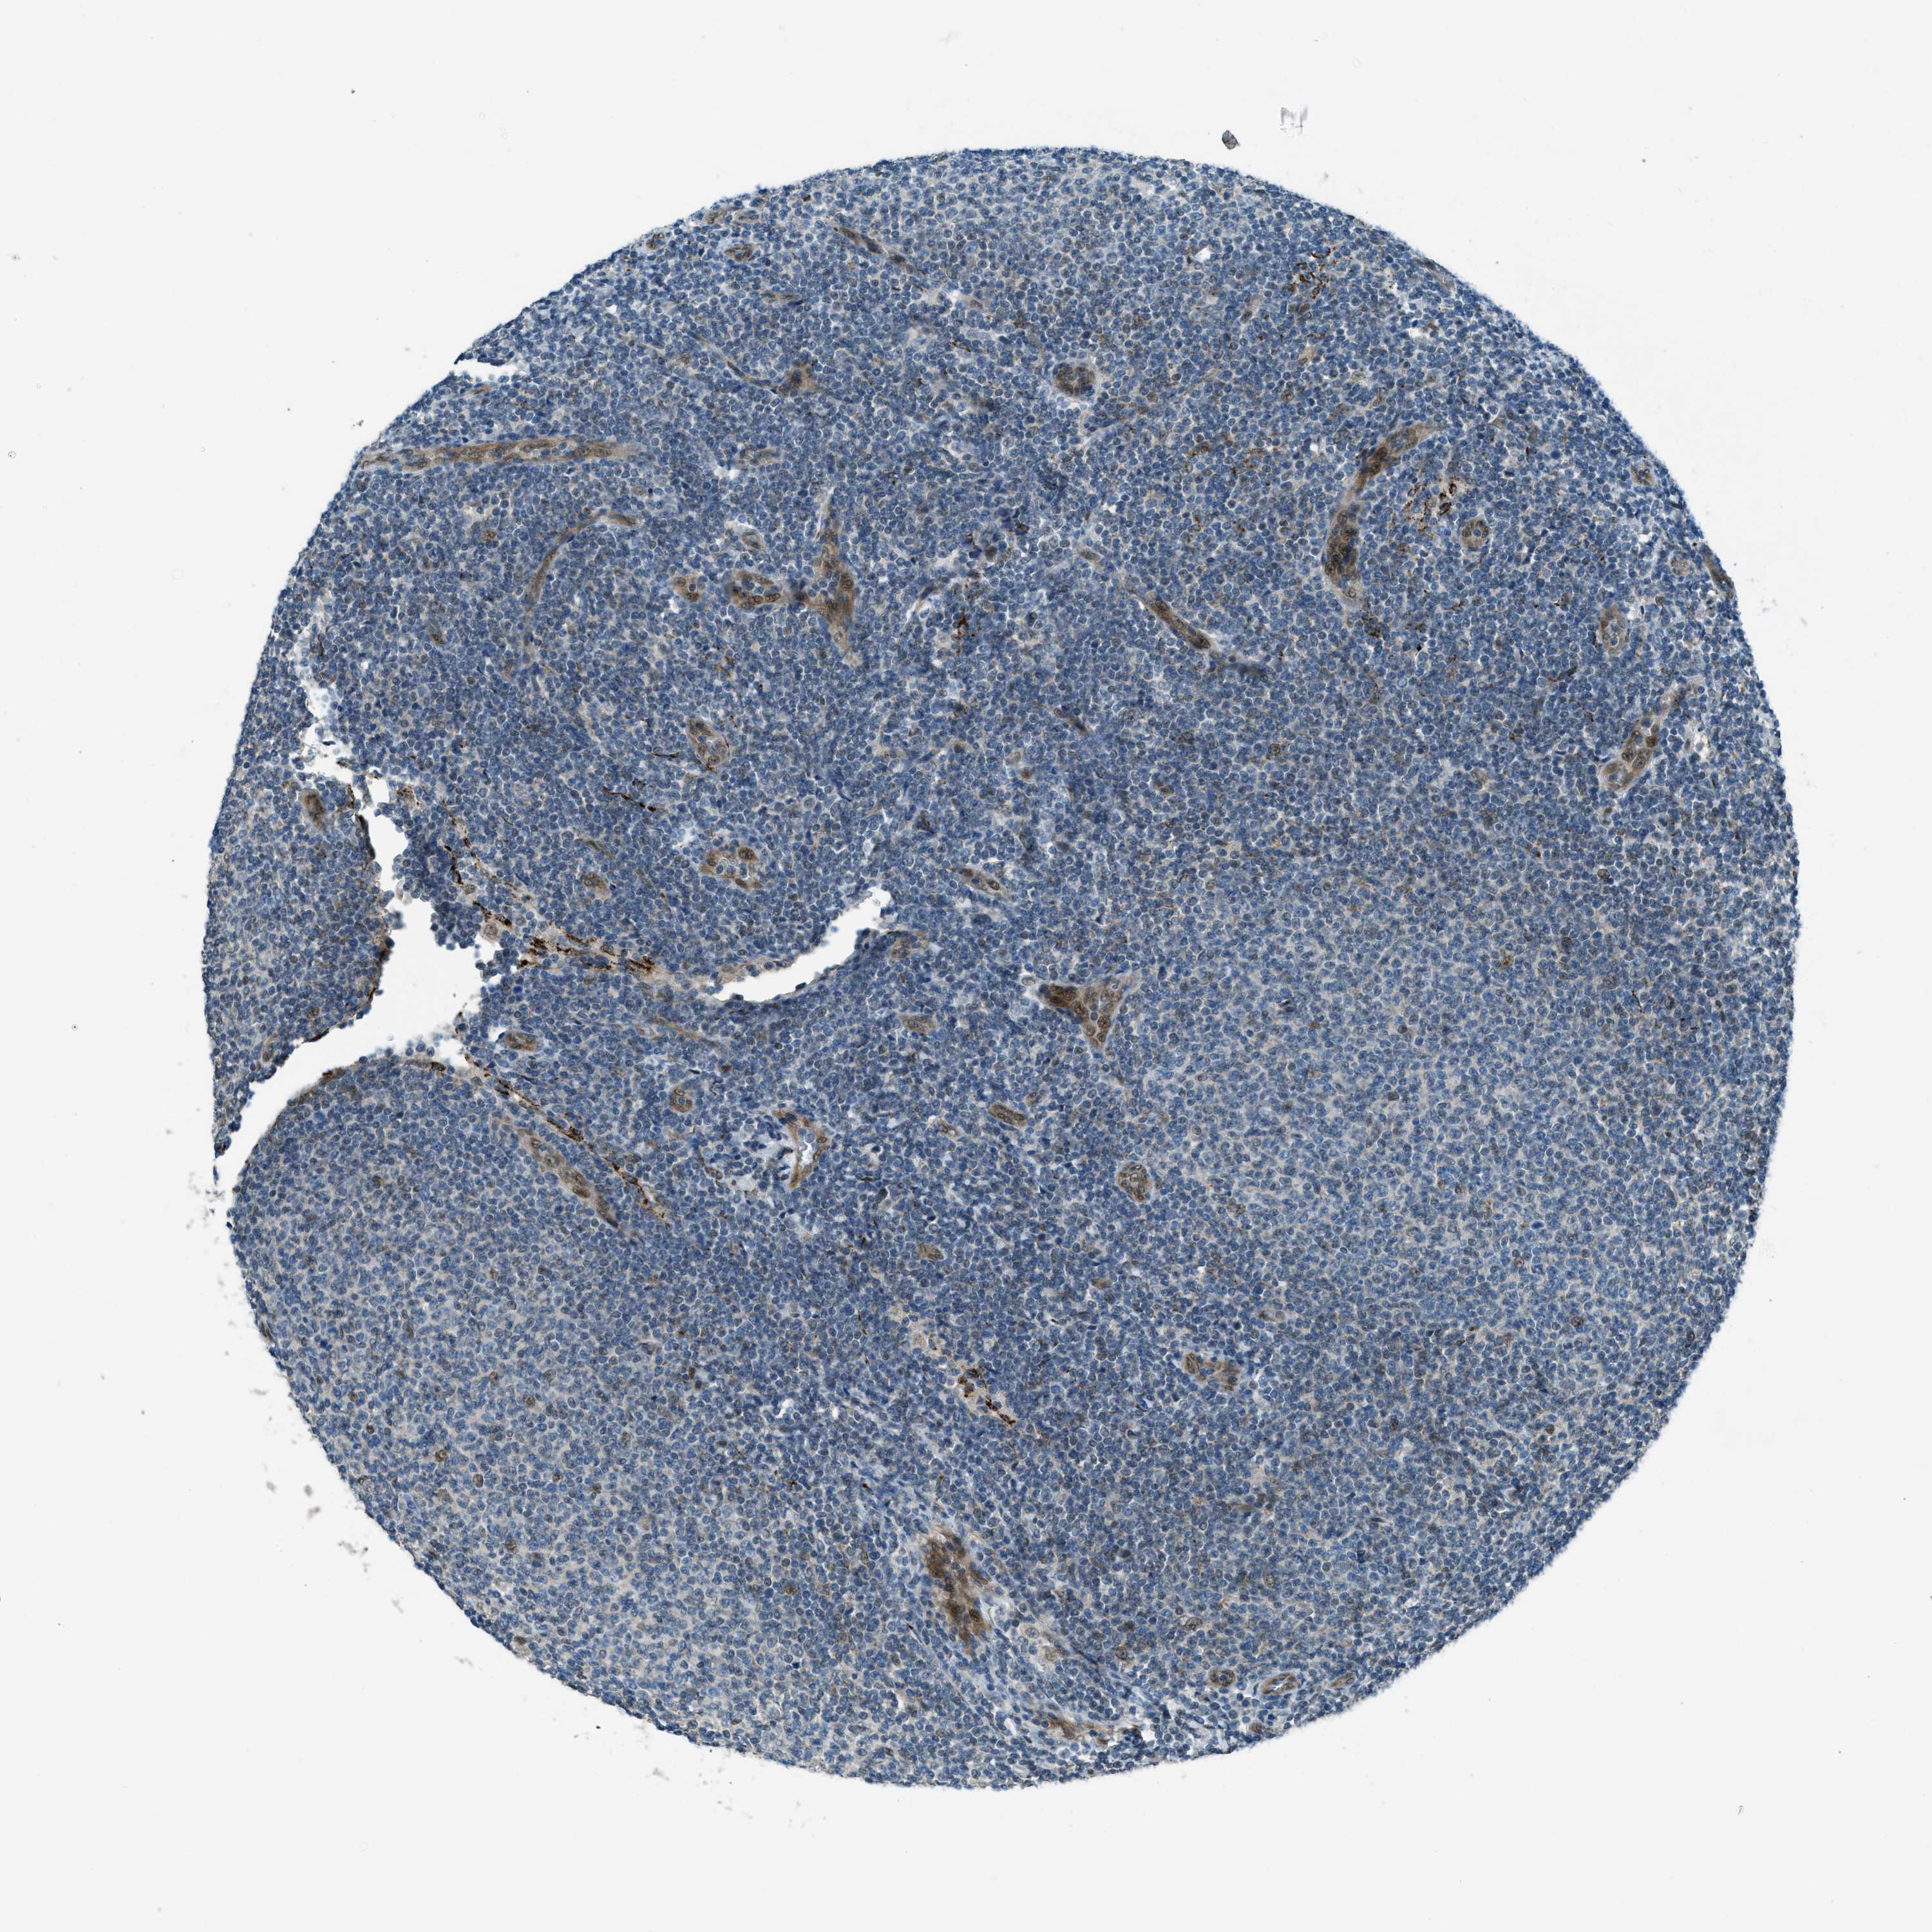

CANCER LYMPHOMA Show tissue menu

LYMPHOMA - Protein expressioni

A mouse-over function shows sample information and annotation data. Click on an image to view it in a full screen mode. Samples can be filtered based on level of antibody staining by selecting one or several of the following categories: high, medium, low and not detected. The assay and annotation is described here.

Each image is clickable and will lead to virtual microscopy that enables deeper exploration of all samples and also displays staining intensity scores, fraction scores and subcellular localization as well as patient and tissue information for each sample.

Antibody HPA036356

Antibody CAB004986

Antibody CAB017025

Hodgkin's disease, NOS

Malignant lymphoma, non-Hodgkin's type, High grade

Malignant lymphoma, non-Hodgkin's type, Low grade